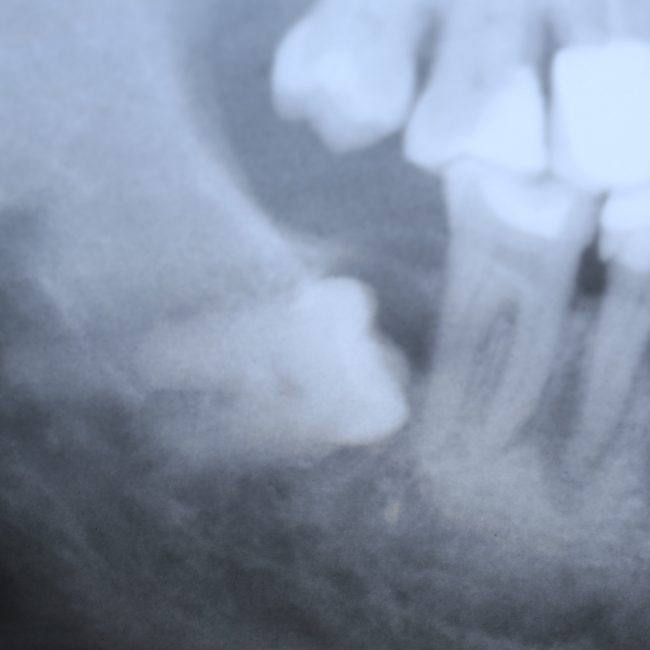

Иными словами, перикоронит может случиться в области любого из зубов, но по стечению обстоятельств, чаще всего случается в области зубов мудрости. Тут я особо подчеркну, что

развитие перикоронита отнюдь не всегда связано с их прорезыванием и нередко происходит уже после него.

Как на картинке ниже: вроде, восьмерка прорезалась давно, но в окклюзионный контакт в антагонистом не вошла. Из-за этого остался десневой капюшон над коронковой частью, усугубленный костным карманом за зубом мудрости. В таких условиях перикоронит случится обязательно — мы только не можем сказать, когда именно.

Поскольку сам человек не в состоянии «промыть» образовавшуюся полость, да и само «промывание» обладает лишь кратковременным эффектом, инфекционно-воспалительный процесс распространяется далее, причиняет дискомфорт пациенту и представляет существенную угрозу для жизни и здоровья.